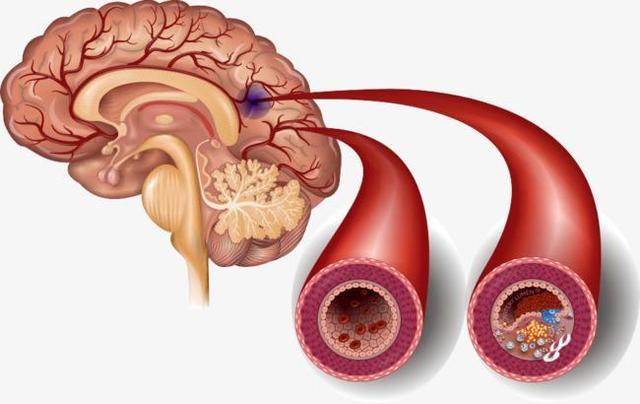

脳血栓症は、実際には脳梗塞の一種であり、脳梗塞の最も一般的な病態である。脳梗塞の多くは、様々な原因(動脈硬化、動脈炎など)により、脳動脈の主幹または一部の皮質枝の内腔が狭窄、あるいは閉塞し、二次的に局所的な血栓が形成され、その結果、脳組織が虚血や壊死を起こし、それに対応する症状や徴候が出現するものである。

脳血栓症は主に内頸動脈系にみられ、一般に大脳梗塞、分水嶺性脳梗塞、出血性脳梗塞、多発性脳梗塞などの病態がある。

1.脳梗塞と脳血栓症の違い:脳梗塞は、脳梗塞、虚血性脳梗塞とも呼ばれ、脳卒中の一種で、最も一般的な脳血管疾患であり、様々な原因で脳血管が閉塞し、脳組織内の血液と酸素が不足して脳組織が壊死し、一連の重篤な症状が現れます。脳血栓症は脳梗塞の一種で、これも脳血管の閉塞が原因である。アテローム性動脈硬化症血管の肥厚、内腔の狭窄および閉塞、血栓症によって形成される。

本当の名称は「動脈硬化性血栓性脳梗塞」といい、脳梗塞の中で最も多いタイプである。脳梗塞は、脳動脈硬化を基盤とするプラークが破裂・潰瘍化し、血管の血栓・閉塞が促進されることによって起こる脳組織の局所的な虚血・低酸素状態を指す。

水道管が錆びたり、老朽化したり、汚れが溜まって管腔が狭くなったり、あるいは詰まったりすると、水は上の階まで流れなくなる。想像してみてほしい。本来10世帯に供給されていた水が、水流が細くなったために1世帯しか使えなくなり、他の9世帯が水不足の影響を受ける。

人体を例にとって言えば、水道管の老化は動脈硬化のようなもので、動脈硬化がプラークを生成するのは「さび色の斑点」、「汚れ」のようなものだ。

違いは、プラークが破裂して血栓症を促進する可能性があることで、これが心血管疾患の急性発作の原因である。